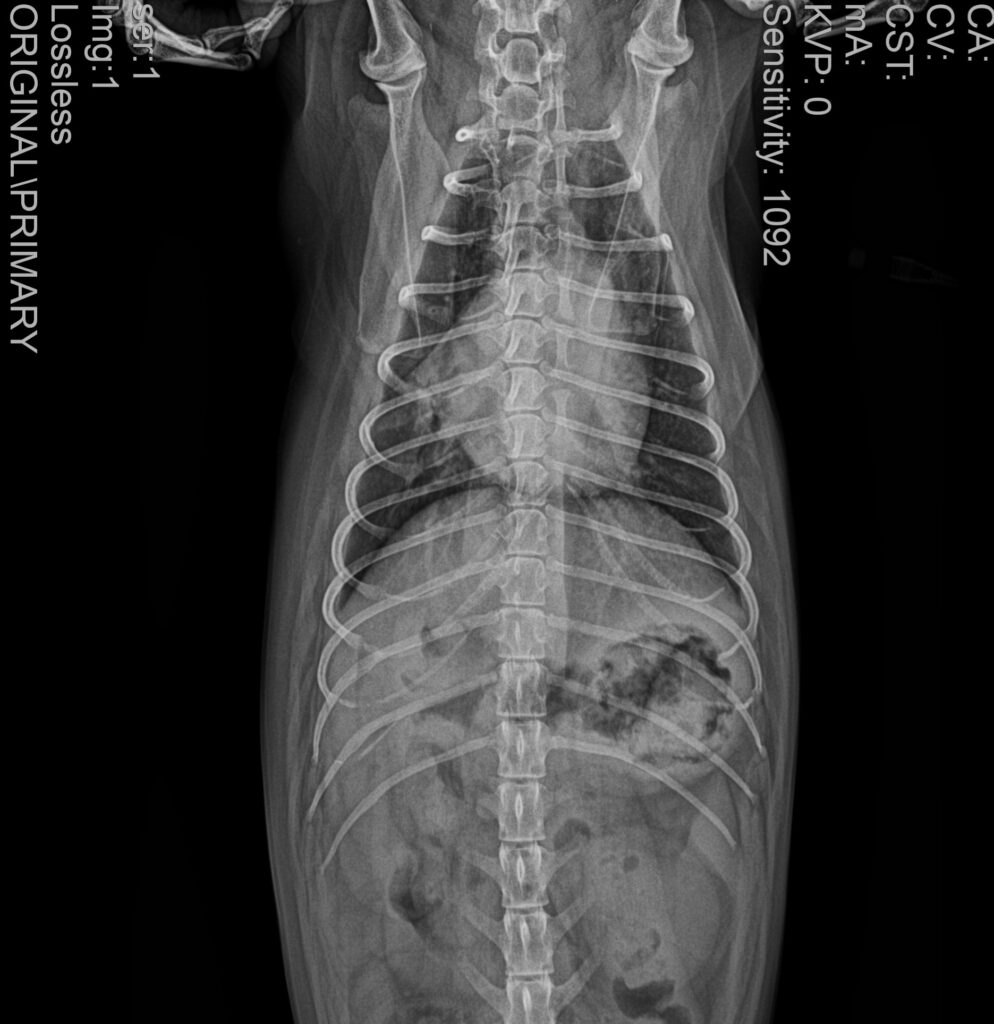

3. 흉부 방사선(X-ray) 검사

흉부 방사선 검사에서는 폐야 전반에 걸친 광범위한 침윤 소견이 관찰되었습니다.

내원 당시 흉부 방사선 사진/ 출처: 강서YD동물의료센터